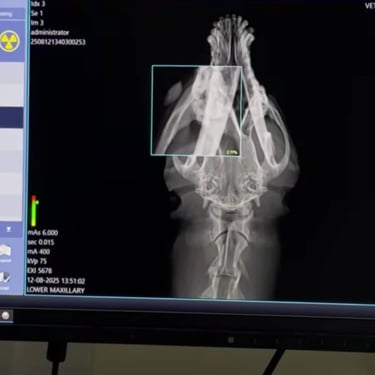

Lucie, chienne martyre de Tunisie. Lucie a été fracassée : oeil arraché et grosse fracture de la mâchoire qui l'ont plongée dans une immense douleur et un profond traumatisme. Le chemin sera long pour réparer son traumatisme moral : elle est tétanisée, mais totalement inoffensive, quand on l'approche, elle se demande ce qu'on va encore lui faire subir ?